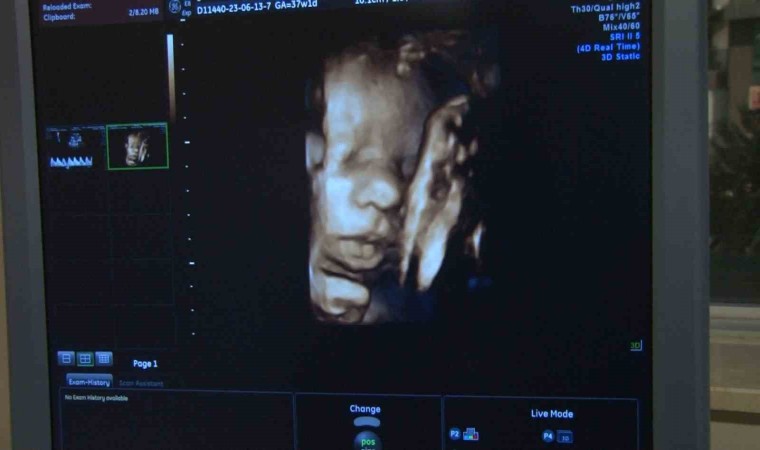

HIV virüsünün kadınlarda olan etkisini ve dünyaya getirdikleri bebeklerin doğum esnasında ya da emzirme süresince bulaştığını ifade eden Kadın Hastalıkları ve Doğum Uzamanı Op. Dr. Sibel Gökmen ise HIV pozitifli annenin gebelik sürecinde tedavisini düzenli bir şekilde alırsa HIV’li bir bebek dünyaya gelme ihtimalinin oldukça azaldığını söyledi. Op. Dr. Sibel Gökmen, “HIV’in anneden bebeğe bulaş yolu gebelik esnasında özellikle üçüncü trimester döneminde, doğum esnasında ya da emzirme süresince olabilir. HIV pozitifli anne gebelik sürecinde tedavisini düzenli bir şekilde alırsa HIV’li bir bebek dünyaya gelme ihtimali oldukça azalmaktadır. HIV’li bir annenin doğum sonrası bebeği emzirmesi önerilmemektedir. Ayrıca gebelik esnasında yapılan tanı ve tarama testleriyle annenin tanısını erken koyulması ve tedaviye başlanması sağlanabildiği için HIV’li bebek doğumları oldukça azalmış durumdadır. HIV’li bir bebeğin hayatını kaybetmesi gibi bir durum yok. HIV aslında Dünya Sağlık Örgütü tarafından kronik bir hastalık olarak değerlendirilmekte ve ömür boyu kontrol altına altında tutulabilmektedir” dedi.